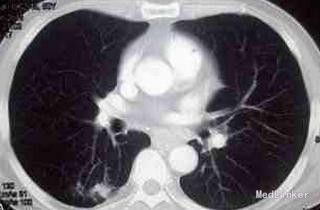

肺隐球菌病为新型隐球菌感染引起的亚急性或慢性内脏真菌病。肺隐球菌为条件致病性菌,其毒力主要在于侵袭力,它能抑制人淋巴细胞的增殖反应。感染后该菌黏附于宿主的上皮细胞,尤其是充血的气道黏膜及其分泌物上,在这种良好的培养基上迅速生长,进一步导致机体免疫力下降。肿瘤患者由于呼吸道防御屏障受损,呼吸功能不全,免疫力下降,真菌易在呼吸道黏膜定植,引起菌群失调而导致内源性感染。